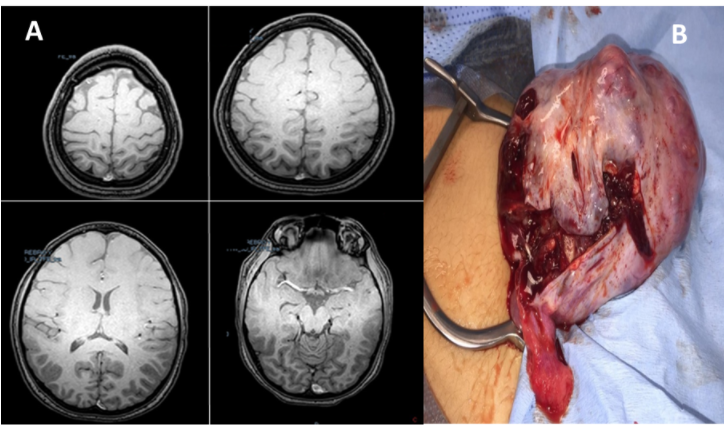

Ingresa con signos vitales TA 110/80 mmHg Fc 90xmin Fr 22xmin T 36ºc SaO2 99%, se considera por parte del especialista solicitar valoración por Neuropediatría quienes solicitan electroencefalograma y RNM de neuroeje (encéfalo, medula cervical, dorsal y lumbar) simples y contrastadas (Estudios reportados dentro de lo normal) (fig. 1). Se hace diagnostico por neuropediatra de pseudocrisis y se decide egresar a la paciente con seguimiento y manejo por psiquiatría con risperidona.

Figura 1:

A) Resonancia magnetica cerebral dentro de límites normales. B) Especimen de patología obtenido.